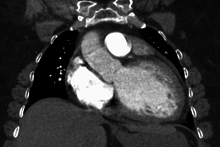

Diagnosis

Generalized enlargement of the heart is seen upon normal chest X-ray. Pleural effusion may also be noticed, which is due to pulmonary venous hypertension.

The electrocardiogram often shows sinus tachycardia or atrial fibrillation, ventricular arrhythmias, left atrial enlargement, and sometimes intraventricular conduction defects and low voltage. When left bundle-branch block (LBBB) is accompanied by right axis deviation (RAD), the rare combination is considered to be highly suggestive of dilated or congestive cardiomyopathy.[19][20] Echocardiogram shows left ventricular dilatation with normal or thinned walls and reduced ejection fraction. Cardiac catheterization and coronary angiography are often performed to exclude ischemic heart disease.

Cardiac magnetic resonance imaging (cardiac MRI) may also provide helpful diagnostic information in patients with dilated cardiomyopathy.[22]